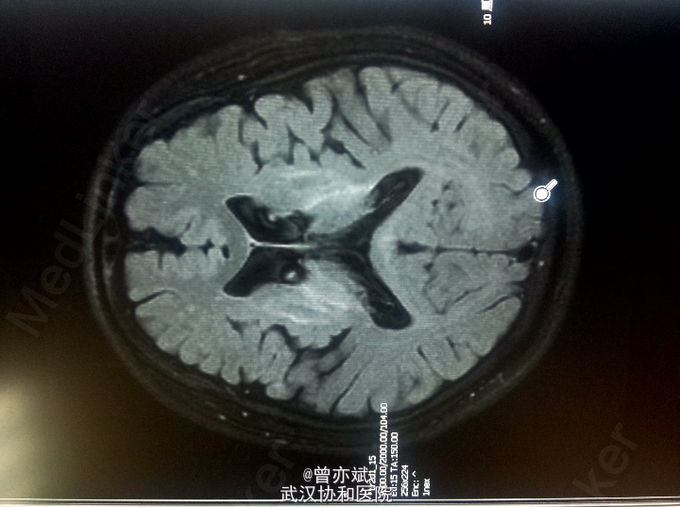

查体:T 36.4℃,P 77次/分,R 20次/分,BP 110/70mmHg。神志清楚,查体合作,皮肤及全身浅表淋巴结未及肿大,心肺腹未及明显异常,双下肢无水肿,生理反射存在,病理反射未引出。 专科查体:神清,吐词不清,语速减慢。双侧角膜可见K-F环,颅神经(-),四肢肌力正常,肌张力减低,左上肢不自主运动,姿势性震颤明显,腱反射对称性活跃,病理征未引出。感觉系统无异常。左手指鼻试验不准。Kernig征阴性。 辅助检查:血常规、尿常规、大便常规、大生化、ENA、ANCA、甲功五项、类风湿三项均阴性,铜蓝蛋白小于20mg/L(正常值220-580mg/L),叶酸、VitB12均正常。MRI平扫+增强 双侧基底节、丘脑、中脑及桥脑、双侧齿状核稍长T1稍高FLAIR信号及双侧苍白球、壳核及黑质信号改变,结合病史考虑肝豆状核变性;脑萎缩,尤以小脑桥脑明显。